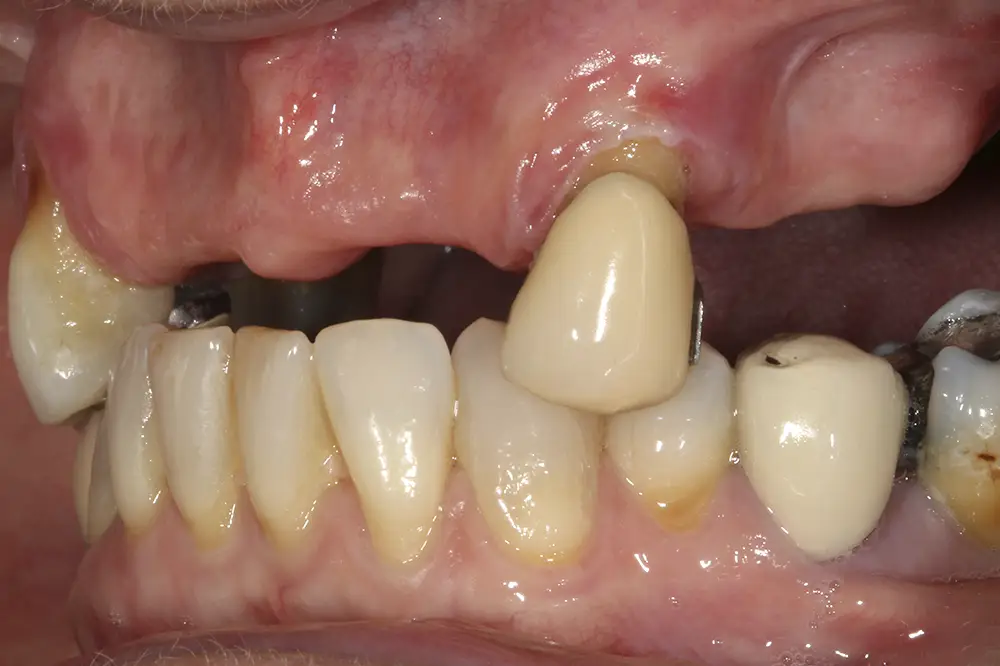

Presentamos el caso de una paciente de 67 años que acude a la consulta demandando tratamiento implantológico para el maxilar superior. Lleva varios años con prótesis removibles parciales, y ha ido perdiendo piezas de manera progresiva. Actualmente, tiene pocas piezas dentales remanentes y las que conserva tiene problemas de movilidad y dolor, por lo que consulta para poder rehabilitar con implantes la zona. En las imágenes iniciales podemos observar el estado de las prótesis removibles y los dientes naturales presentes (figs. 1-4)

Figs. 1-4. Imágenes iniciales de la paciente, donde observamos el estado de la prótesis removible que porta la paciente frontal y lateralmente, así como los dientes remanentes.